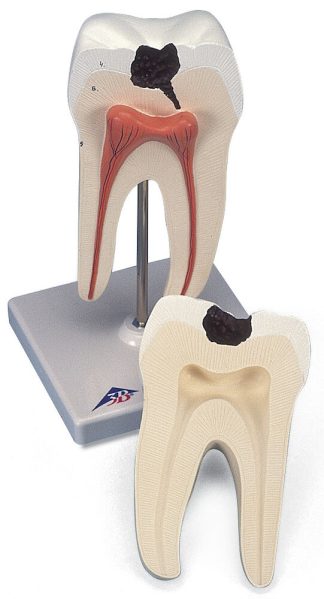

Innehåller 10 bilder som vid vinkling ändras och visar vad som händer i våra största organ i kroppen.

Innehåller bl.a. Hjärtat, Lungorna och hjärnan mm.